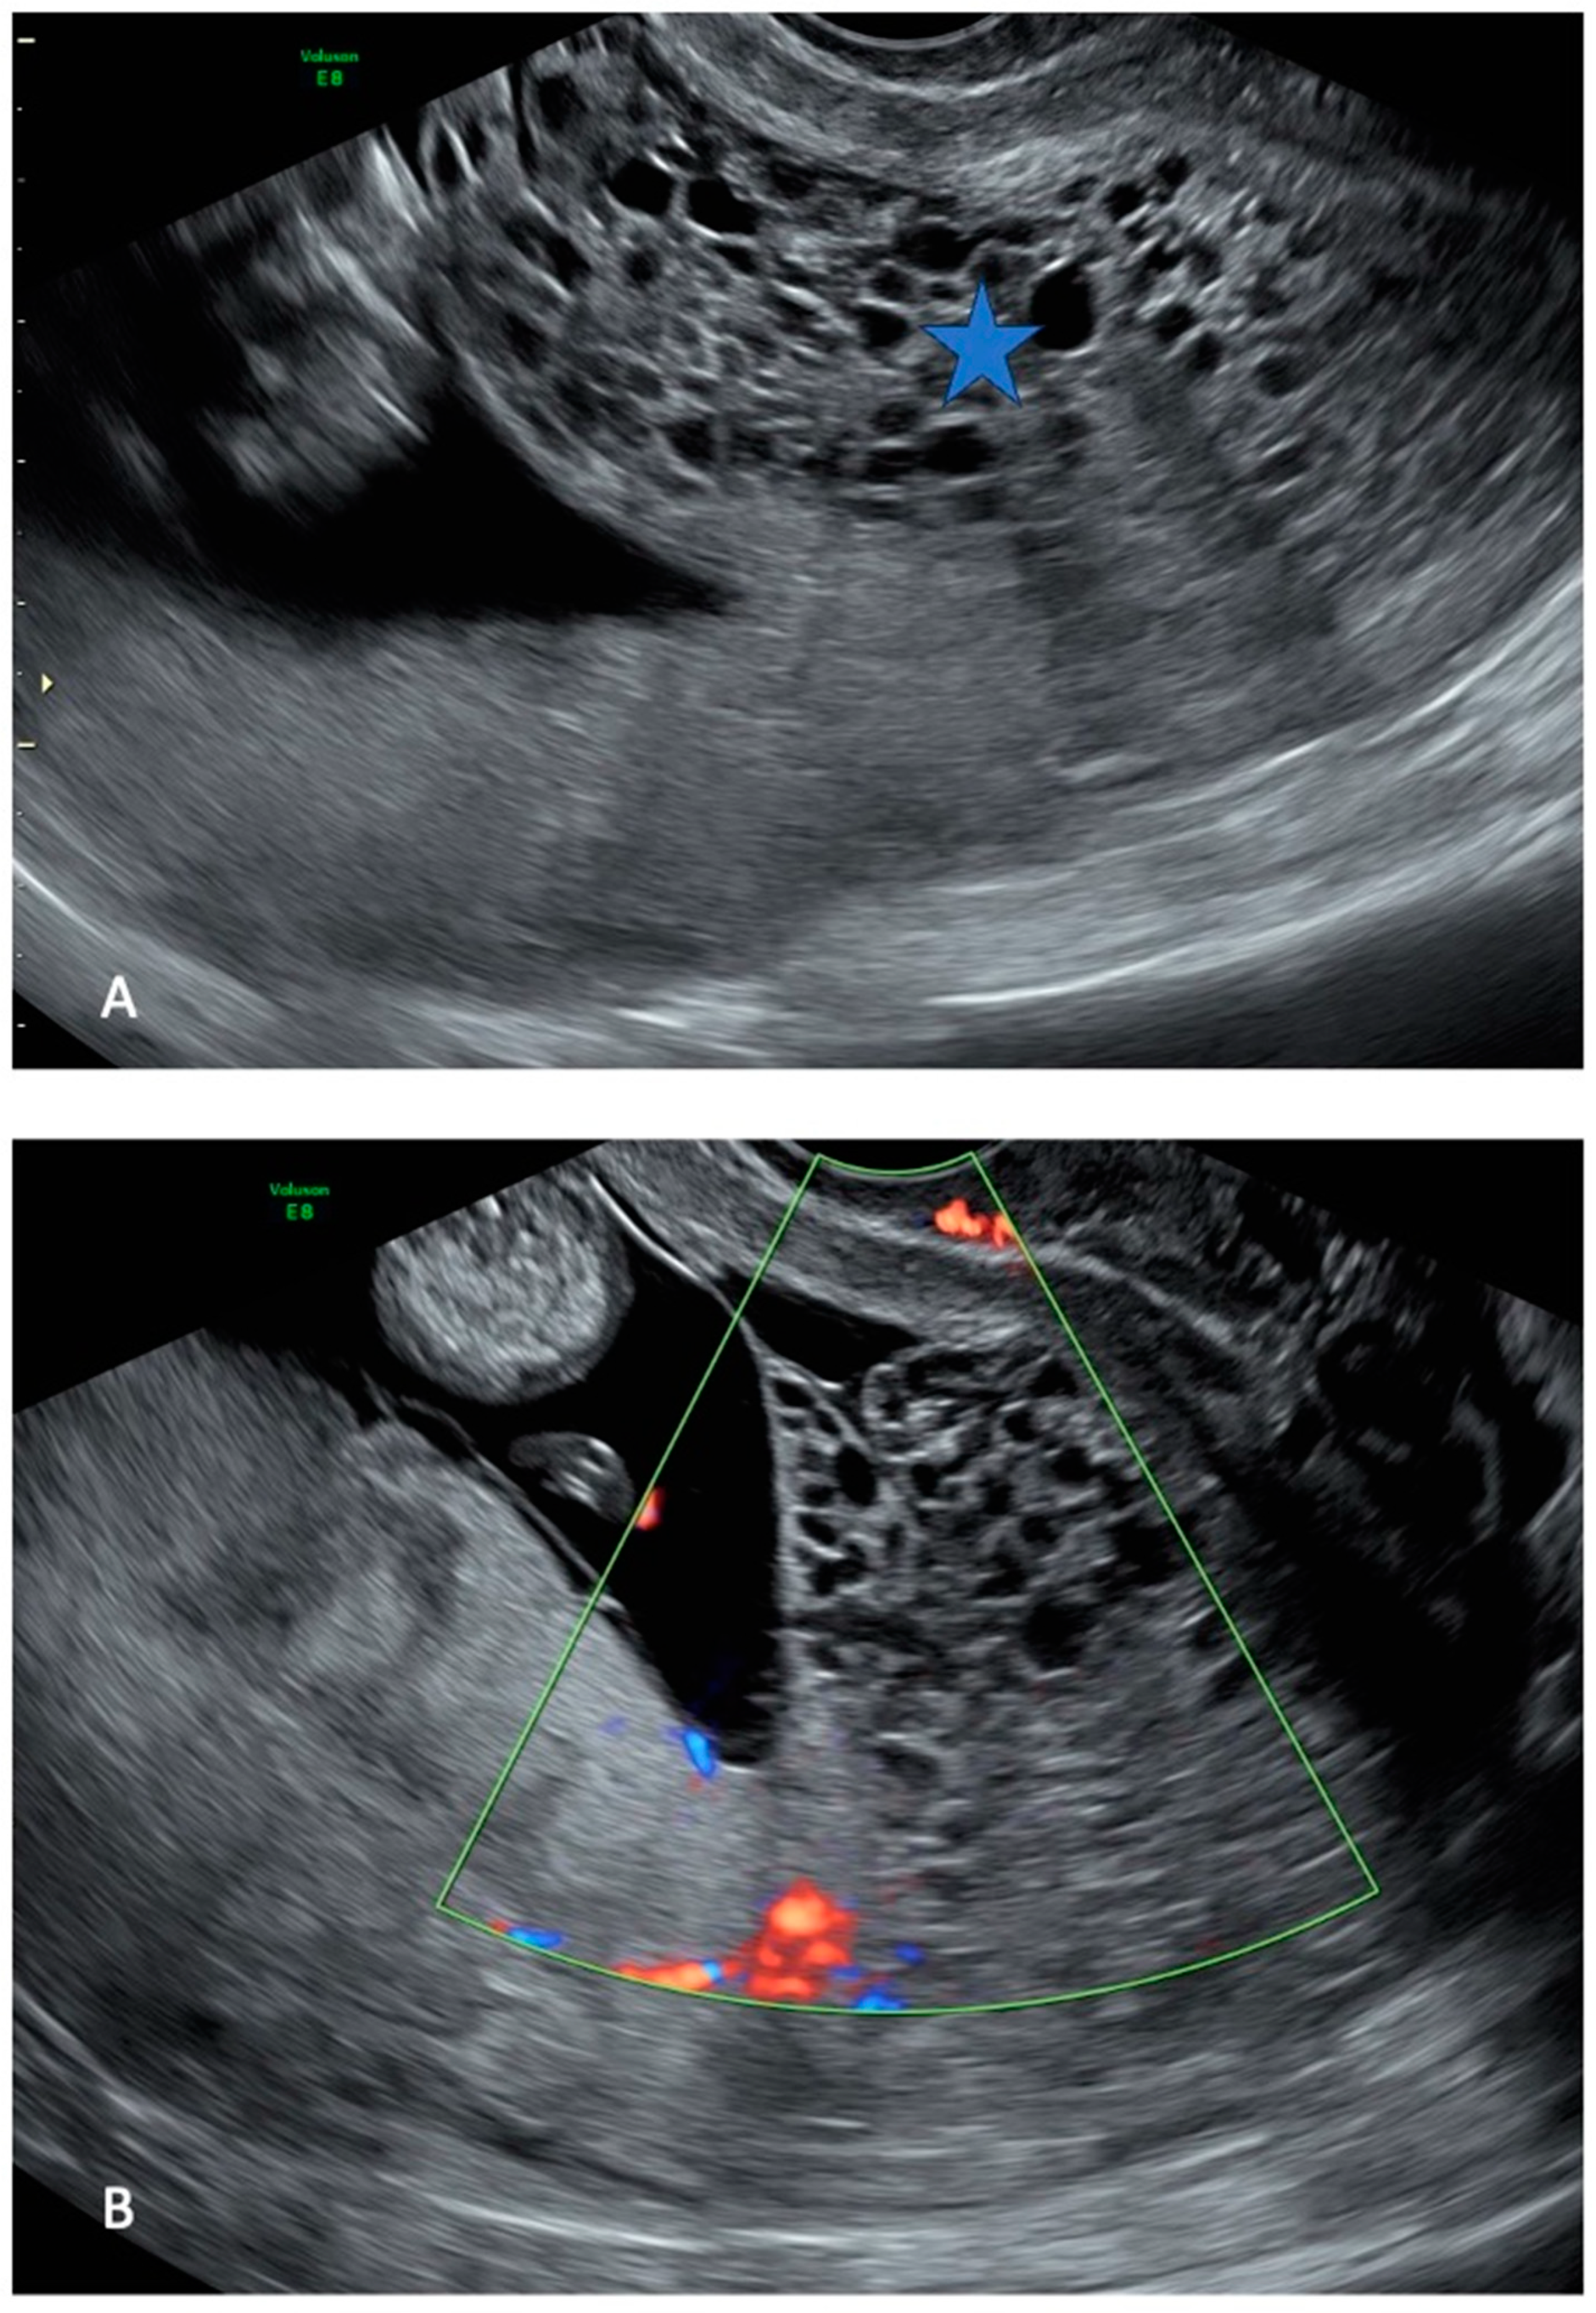

The referred US revealed an intrauterine pregnancy with a live fetus of normal size and morphology. US examination showed one placenta with a regular appearance, and adjacent to it, a cystic placental mass, measuring 70 × 50 mm (Figure 1).

Ultrasound images of hydatiform mole at 13 weeks of gestation: a normal intrauterine pregnancy ((A,B) left side) coexisted with a multicystic area ((A) star, (B) echographic cone), compatible with molar degeneration.

Considering the US finding of a second cystic placental mass in the absence of fetal structures, the clinical picture of vaginal bleeding, and the biochemical profile showing elevated maternal beta-hCG levels, a presumptive diagnosis of CHMCF was made. Although the definitive histological diagnosis, which could only have been made through bioptic sampling, was not pursued, the US images were sufficient in providing thorough counseling to the couple regarding maternal risks associated with pregnancy progression or legal TOP. In particular, the couple was informed that, according to data from the literature, the risk of preeclampsia and IUGR associated with the specific clinical condition could have been as high as 25% [9,11].